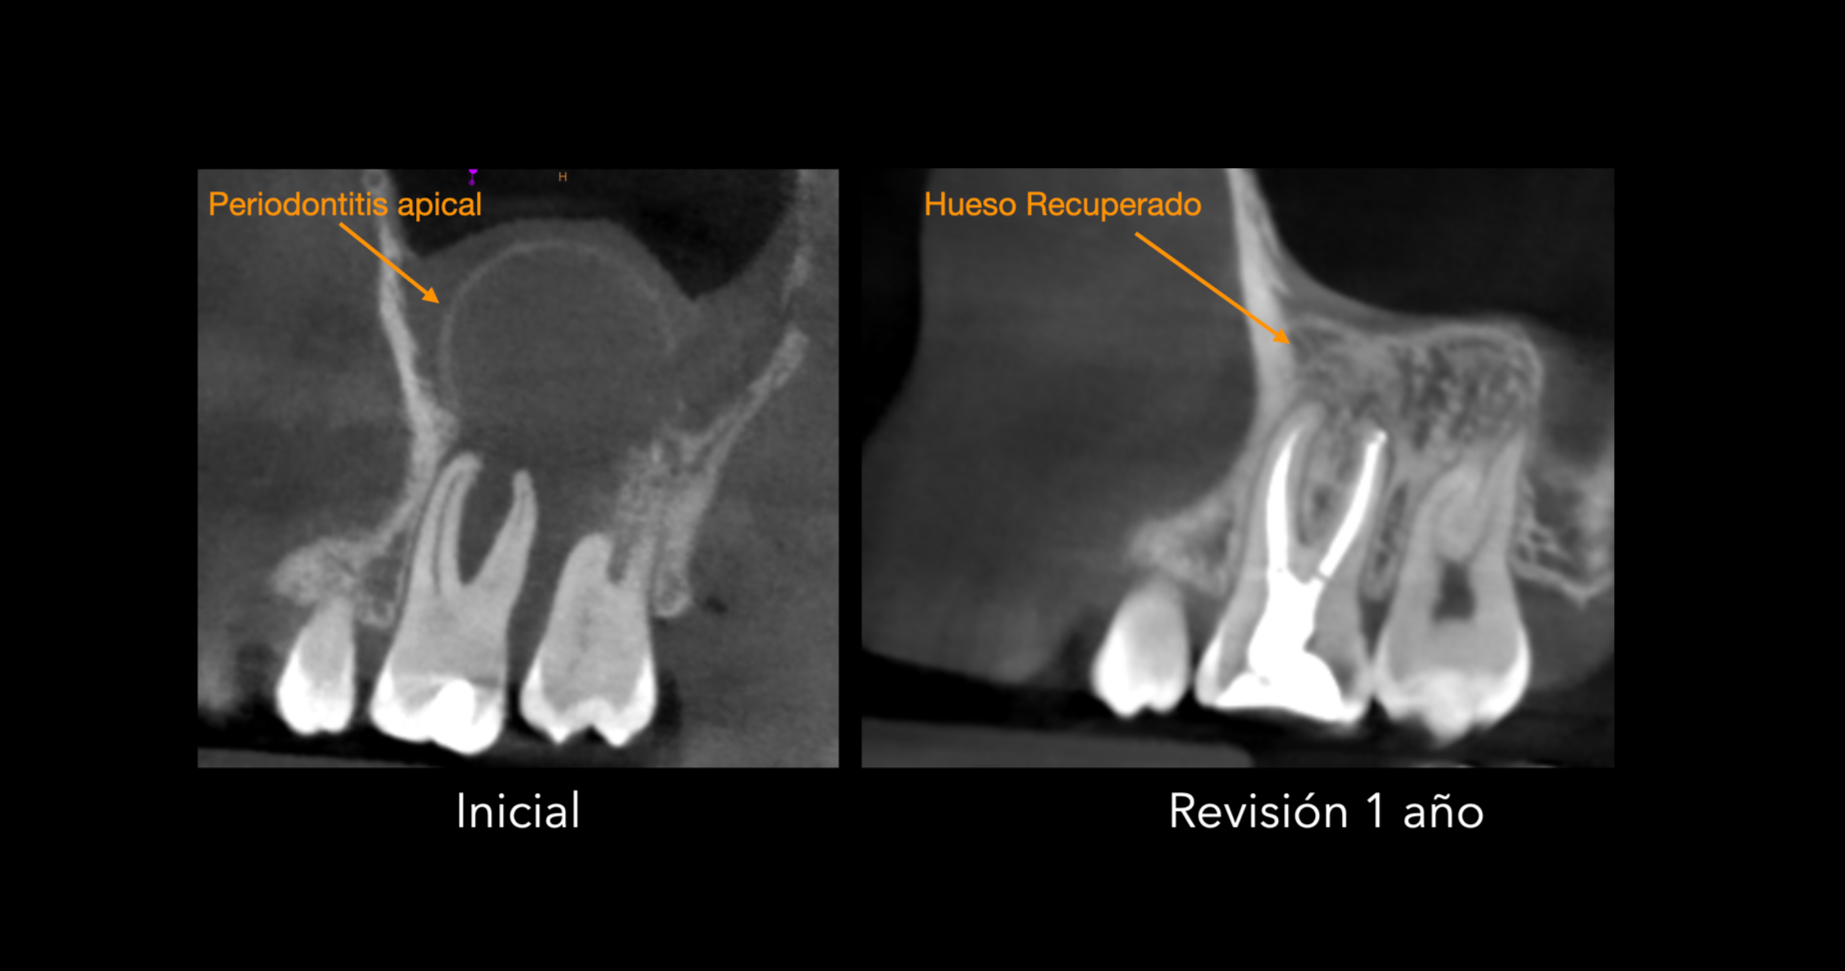

Generamos Hueso

Generamos hueso sin cirugía.

El tratamiento de conductos consigue regenerar el hueso perdido y con ello salvamos el diente del paciente.